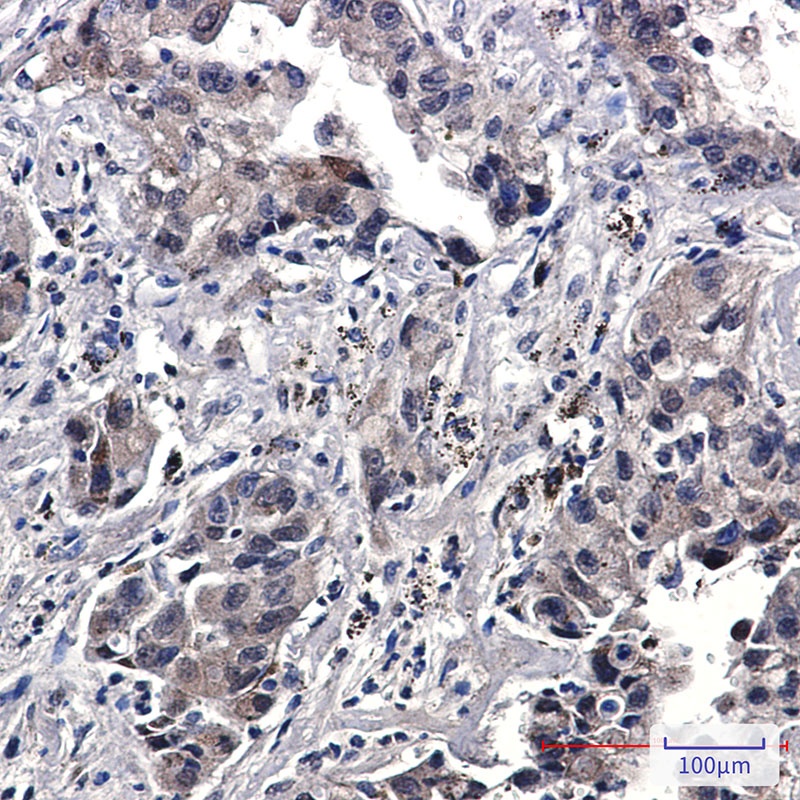

过程中,一抗应在封闭缓冲液 (TBS/0.3%Triton. X–100/5% NGS) 中稀释。抗体:Phospho–Akt (Ser473) (D9E) XP. Rabbit mAb #4060、Phospho–EGFReceptor (Tyr1173) (53A5) Rabbit mAb #4407样本:石蜡包埋人类乳腺肿瘤(上图)和 HCC827 异种移植物(下图)抗体稀释:SignalStain. 抗体稀释液(左)或 TBST/5%NGS(右)检测—检测系统传统的 IHC 检测